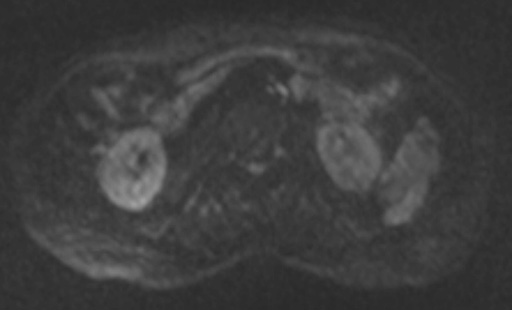

図5 T2強調横断像 図6 拡散強調横断像(b=1000)

図6 拡散強調横断像(b=1000) 図7 ADC画像